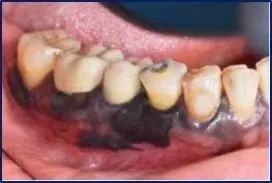

从颜色上看:口腔黑色素瘤表现为明显的蓝黑色结节状肿块。从生长速度看:口腔黑色素瘤生长速度十分迅猛,颜色加深,并向四周扩散生长。

从形态上看:一般表现为斑点或者结节状,表面常溃烂。

从发病位置看:口腔恶性黑色素瘤大多数出现在上牙龈以及硬腭,也有部分病例病变位置出现在颊部、舌部以及唇部。